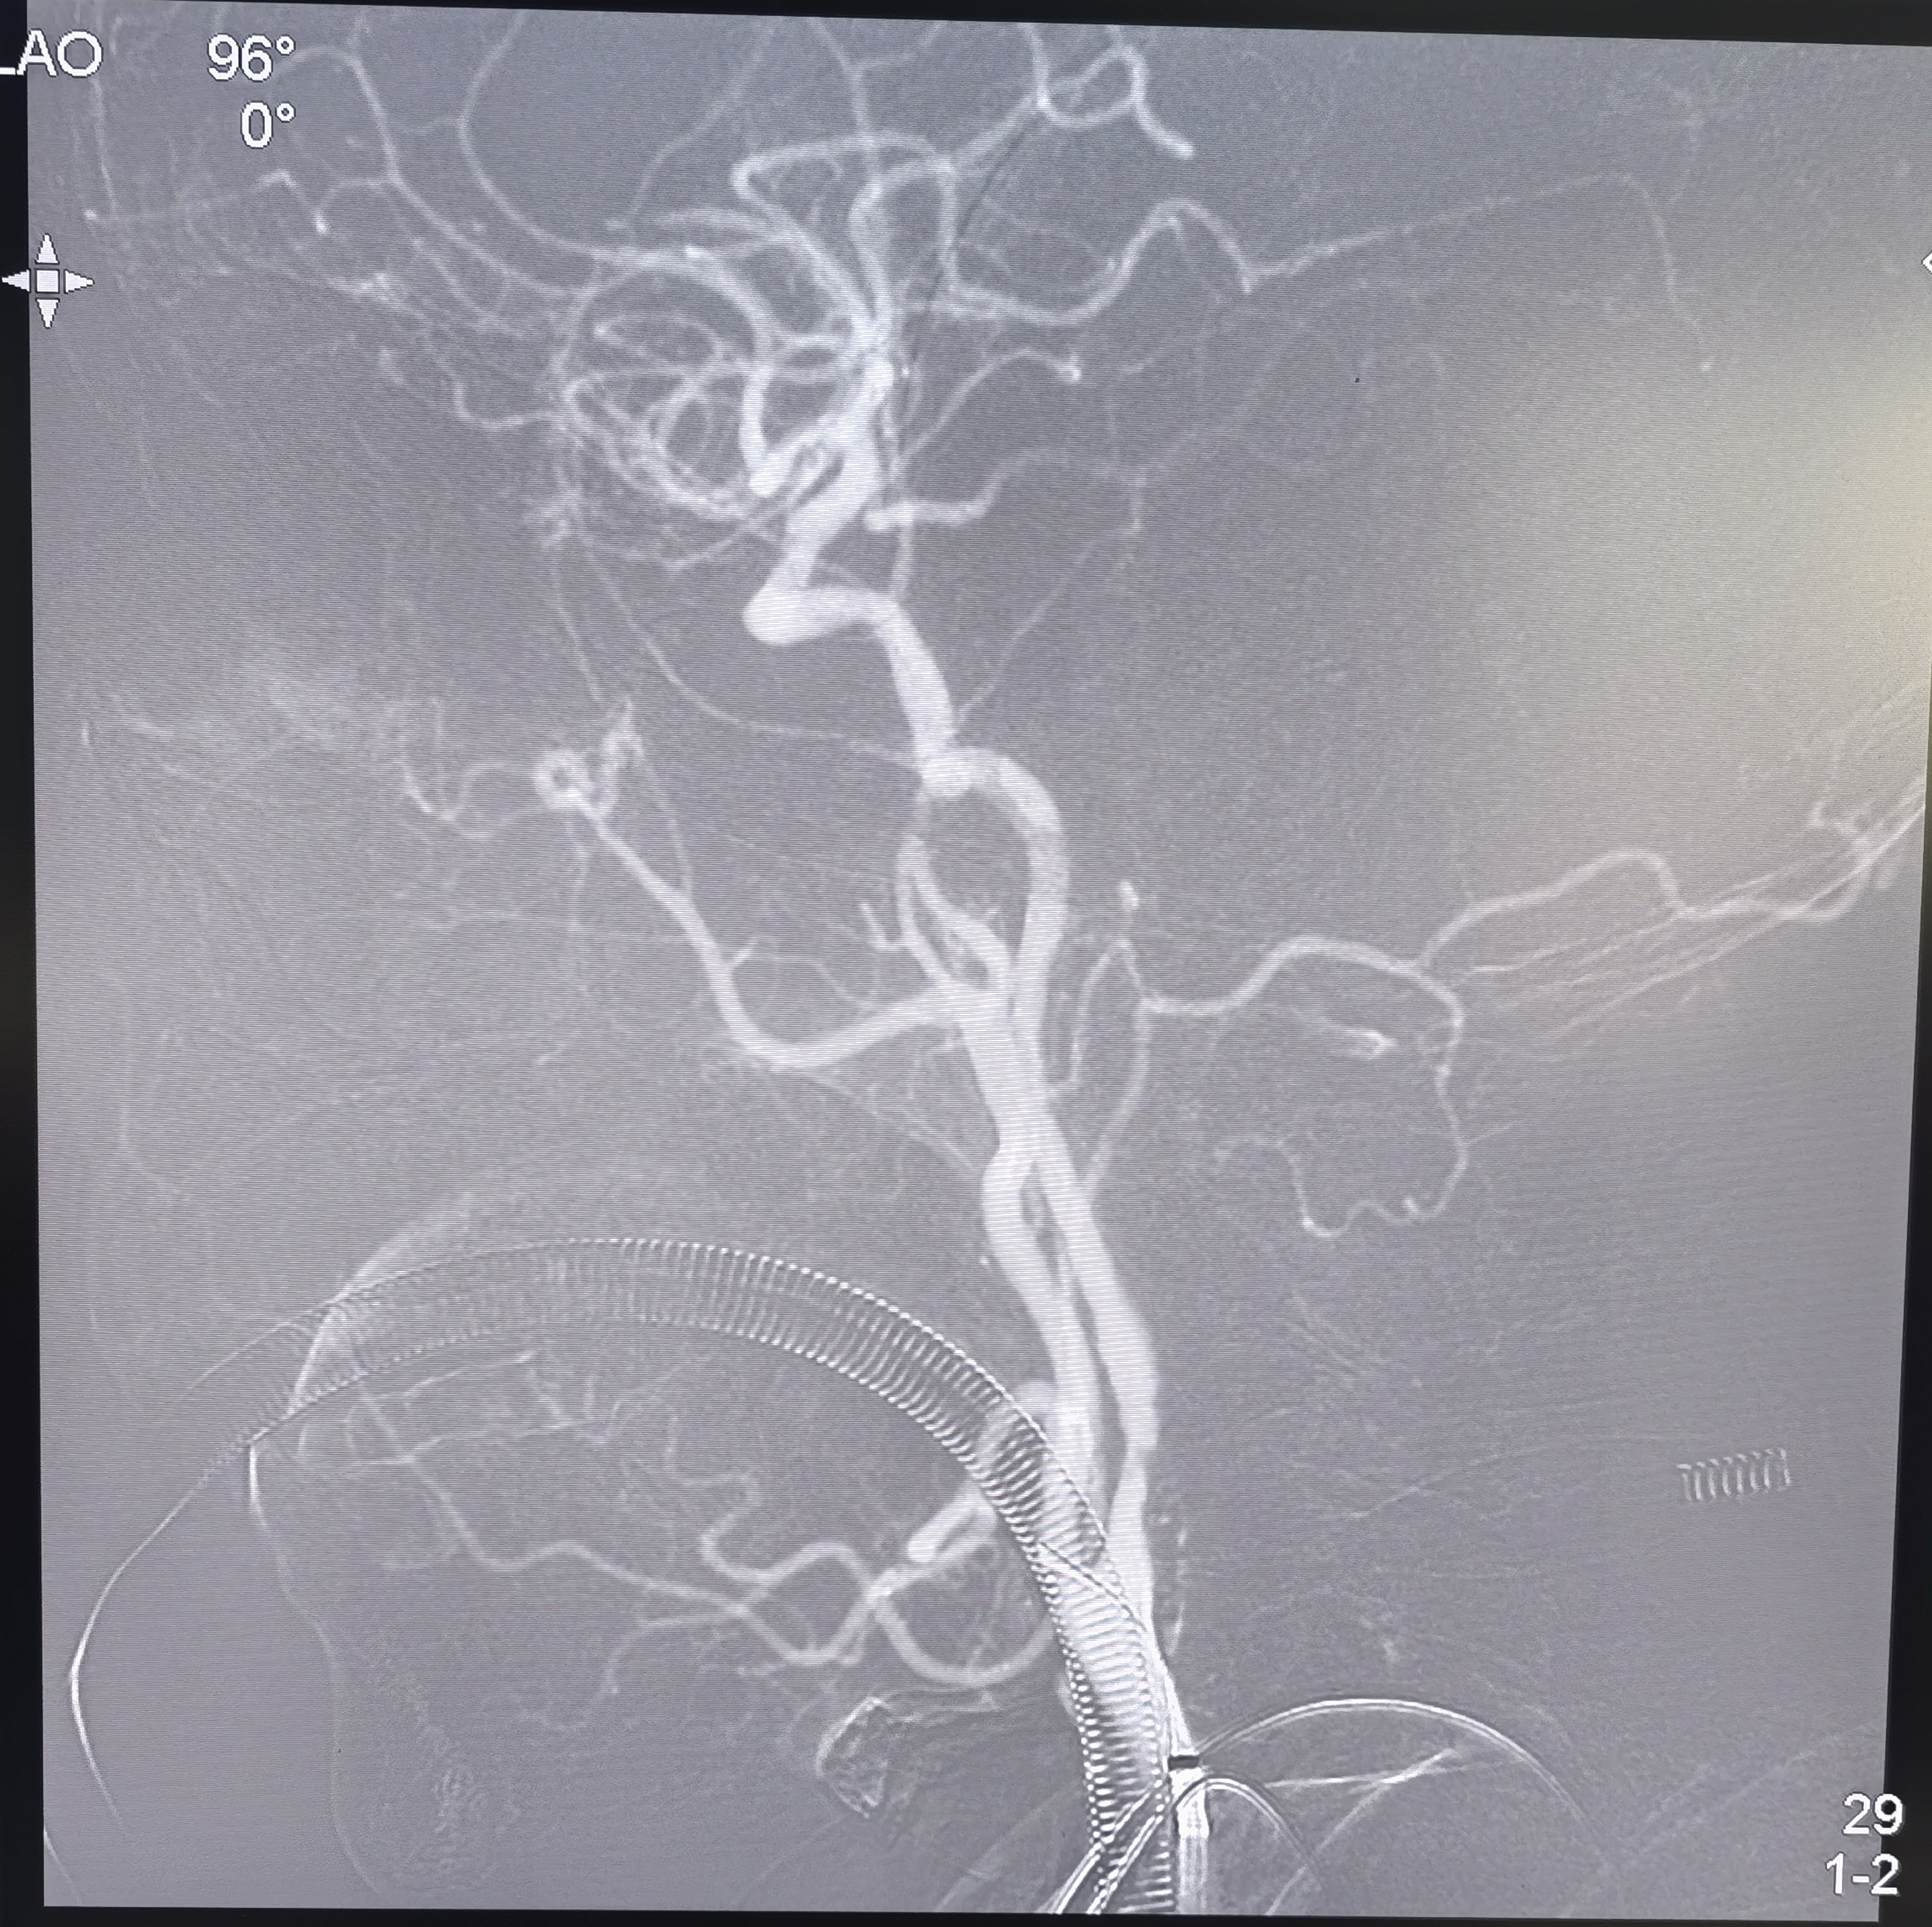

支架置入后造影侧位

支架置入后造影正位